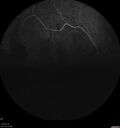

PDR and Vitreous hemorrhage - Second FA is following PRP laser256 views42 year old man (date 2018): Prior to 2 months ago the vision in the right eye was good. This started with a glob in the vision and then the vision got better. Then the string came back down and is getting bigger and bigger. The last time he had bleeding in the left eye he had surgery in 2009. The left eye is now doing OK other than there is a cataract. The right eye had some laser treatment done in 2009. The vitrectomy and laser were done at William Beaumont.

VA OD: sc3'/200 NscUnable

VA OS: sc20/40 NscJ2-1